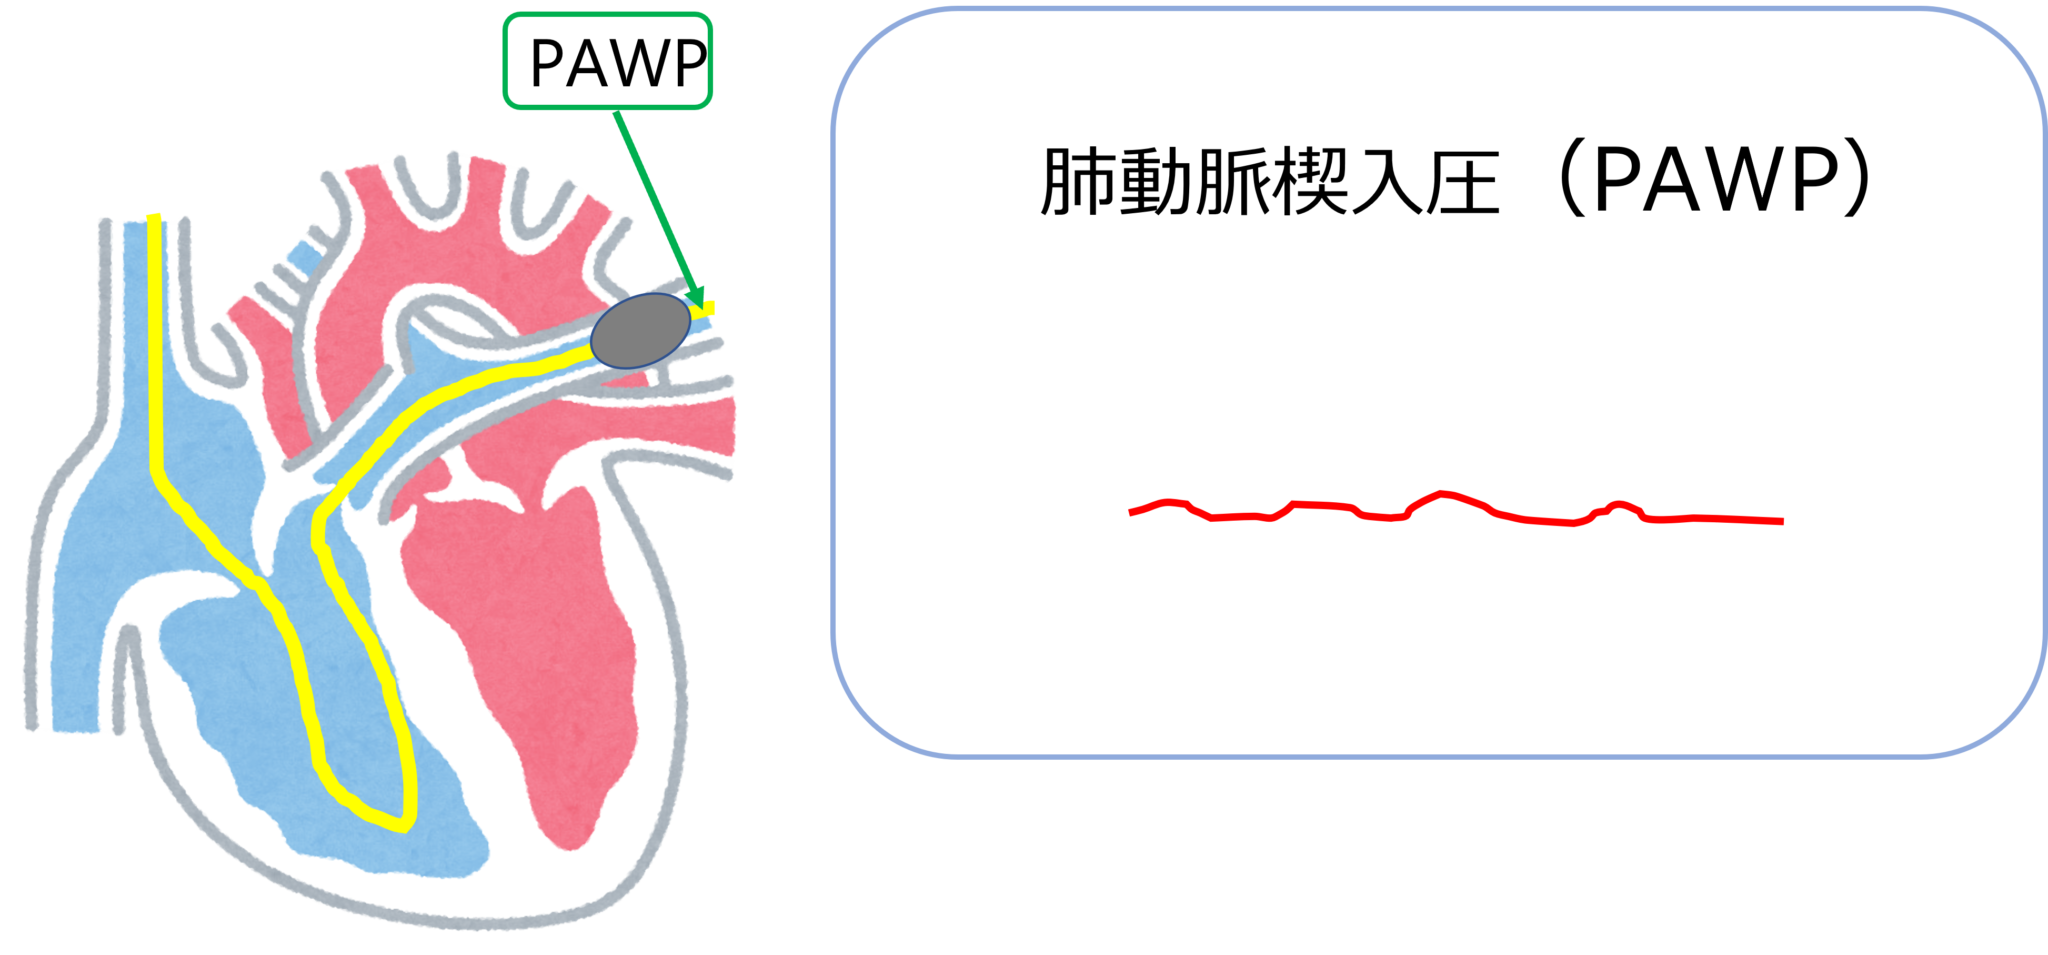

この手順では、肺動脈カテーテル (PAC) を心臓の右側と肺につながる動脈に挿入します。 PAC にはバルーンチップが付いています。バルーンを使用すると、カテーテルを血液の流れに乗って心臓内の使用場所まで運ぶことができます。

この処置自体は、右心カテーテル法と呼ばれることもあります。これは、心臓の右側を流れる血液の圧力を測定できるためです。 3 つの異なる場所で圧力を測定します。

- 肺毛細血管

これらの測定値は、心臓の適切な部分の血液中の酸素量を把握するために使用できます。また、心臓から全体的にどれだけの血液が流出するかを把握するためにも使用されます。